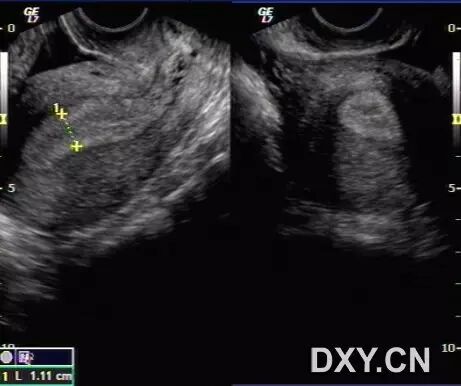

病例1(由丁香园注册用户「微蓝水色」提供):26岁女性,已婚,自觉腹胀不适就诊。

超声检查发现子宫大小正常,双侧附件区多囊性包块,盆腔大量积液,胸腔积液。肝胆胰腺肾脏及膀胱未见明显异常声像。

追问病史,患者多囊卵巢治疗后拟怀孕,最近正服用促排卵药物。

患者治疗后两周复查,盆腹腔积液消失,胸腔少量积液,附件包块明显缩小,能够分辨出卵巢形态。

结合病史,考虑为卵巢过度刺激综合征表现。

以下图片为第一次检查时的图片:

图1 显示子宫周边积液

图2 和图3 显示卵巢增大,其内见多个增大的卵泡样结构